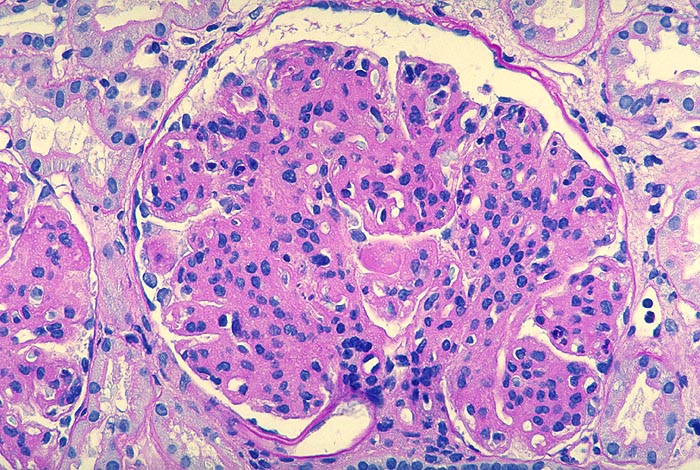

Membranoproliferative Glomerulonephritis: lobuläre Variante

Starke mesangiale Sklerose und ausgeprägte mesangiale Hyperzellularität. Die peripheren Kapillarwände sind stark verdickt. Stellenweise lässt sich eine mesangiale Interposition vermuten. Im Zentrum finden sich Kapillarschlingen, die durch plumpe Proteindepots nahezu vollständig verschlossen sind.

Phasischer Ablauf:

Initial finden sich in den Schlingen subendotheliale Immundepots begleitet von gelapptkernigen Leukozyten und Monozyten.

Mit Abnahme der endokapillären Hyperzellularität kommt es zu einer mesangialen Zellproliferation mit Auswandern der Mesangiumzellen in die Peripherie und Neubildung einer Basalmembran (mesangiale Interposition).

Schliesslich verschwinden die subendothelialen Depots, die neugebildete Basalmembran wird dicker, die Mesangiumzellzahl nimmt ab und die mesangiale Sklerose zu.